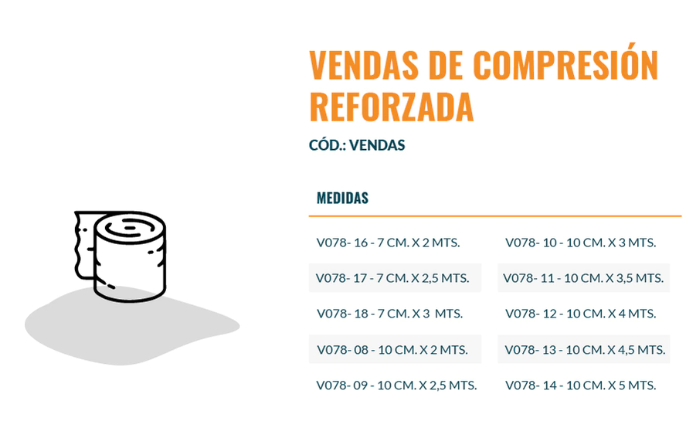

Medidas

10 cm x 5 m.